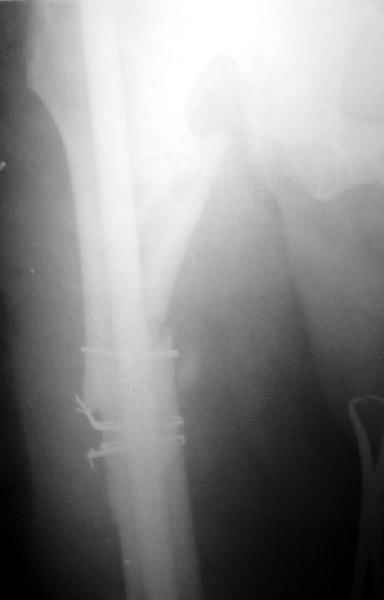

На данный момент правая голень срослась, больной активен в пределах постели. Второе(правое) бедро стабилизированное (рис. до и после). движения в коленном суставе: сгибательная контрактура правого коленного сустава 90, левого 145.